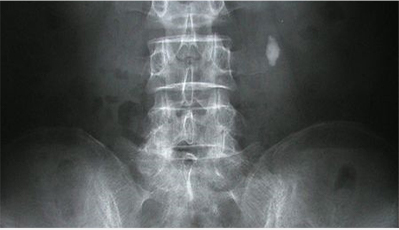

혈뇨 증상이 있을 때 초기 검사로 복부단순촬영을 시행할 수 있습니다. 혈뇨의 원인이 되는 결석의 초기 발견에 중요한 역할을 합니다.